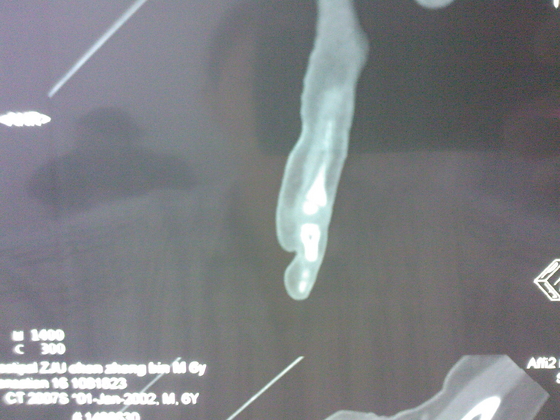

把病理送浙一医会诊后诊断为:骨外软骨瘤。同时做了CT检查。暂未予治疗。

今天把创面情况跟CT发上请大家看看。

继续还有几张。